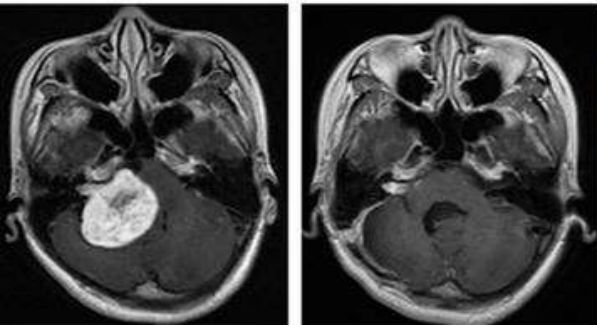

治疗期间,吴女士唾液分泌、皮肤、甲状腺无显著影响。治疗后MRI显示鼻咽左侧壁的局部复发已经明显缩小。两个月后吴女士开始正常上班。目前随访,病情处于稳定状态。